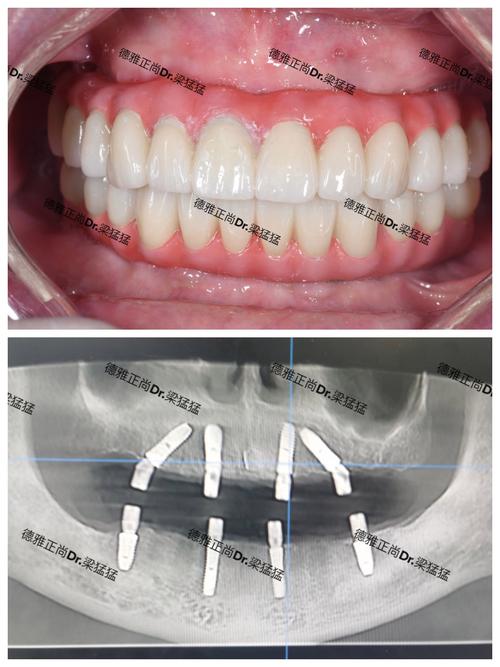

- 医生经验与技术: 种植牙的核心在于医生! 了解主诊医生的种植经验(从业年限、种植数量)、技术风格、是否接受过系统培训、擅长哪些种植系统(如ITI、Nobel、Osstem、Dentium等)和种植技术(即刻种植、微创种植、All-on-4/6等),要求查看医生的资质证明和成功案例。

- 设备与材料: 是否配备先进的设备,如口腔CBCT(锥形束CT)、数字化口内扫描仪、种植手术导板等?使用的种植体品牌、基台、牙冠材料是什么?不同品牌和材料价格差异大,质量和长期效果也不同,常见的进口品牌有瑞士Straumann(ITI)、瑞典Nobel Biocare、德国Ankylos、美国Zimmer、韩国Osstem/Dentium等;国产品牌也在快速发展。

- 拍片检查是必须: 没有CBCT等影像学检查,医生无法准确评估您的骨条件,无法制定科学安全的种植方案。